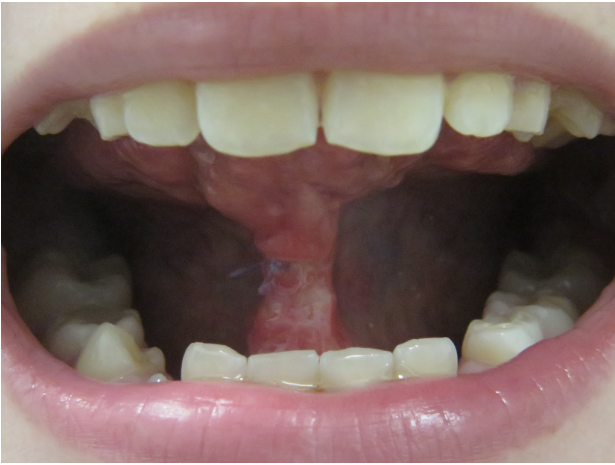

Wir sagten es bereits an anderer Stelle – Bilder sagen mehr als 1000 Worte…

Die Galerie zeigt verschiedene Problemstellungen unserer Patienten von Anfang bis Ende:

mykie® macht’s möglich – sehen Sie selbst: